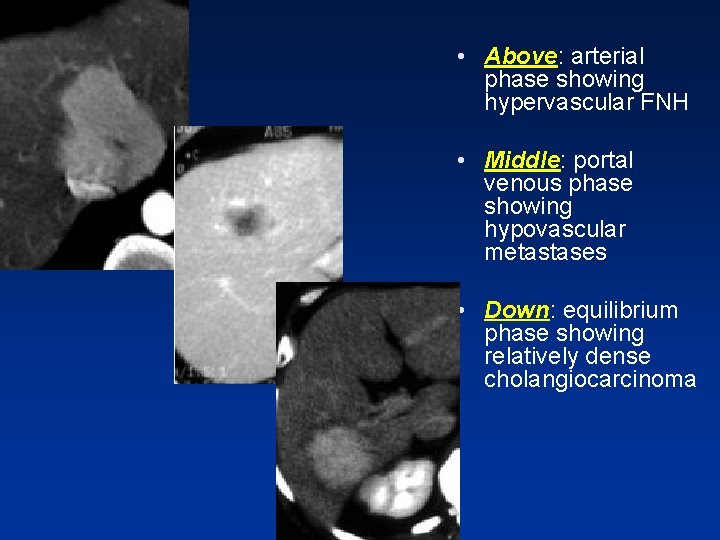

• Above: arterial phase showing hypervascular FNH • Middle: portal venous phase showing hypovascular metastases • Down: equilibrium phase showing relatively dense cholangiocarcinoma